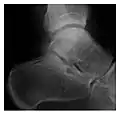

a

b

Figure 7: Fatigue fracture of the talus in a 25-year-old male basketball player with right hind foot and ankle pain, without history of trauma, and a normal initial radiograph (not shown). (a) One-month followup lateral radiograph shows normal appearance. (b) Sagittal T1-weighted MRI shows an irregular fracture line (arrow) within an ill-defined area of hypointensity corresponding to bone marrow edema.[1]